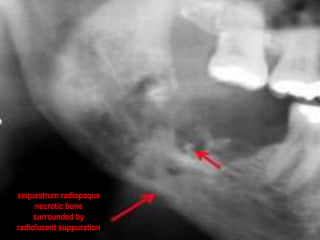

 Chronic osteomyelitisusually demonstrates bony destruction in the area of infection. The appearance is one of increased radiolucency, which may be uniform in its pattern, or patchy with a moth-eaten appearance. Areas of radiopacity also may occur within radiolucency. These radiopaque areas represent islands of bone that have not been resorbed and are known as sequestra. In longstanding chronic osteomyelitis, an area of increased radiodensity surrounding the area of radiolucency, called an involucrum, may be present. This is the result of a reaction in which bone production increases as a result of the inflammatory reaction.

 --Diagnosis ofosteomyelitis is often based on radiologic results showing a lytic center with a ring of sclerosis. Culture of material taken from a bone biopsy is needed to identify the specific pathogen; alternative sampling methods such as needle puncture or surface swabs

Involucrum A sheath ofnew bone separated from the sequestra by a zone of radiolucency. sequestrum (radiopaque necrotic bone surrounded by radiolucent suppuration) Wire for fixation